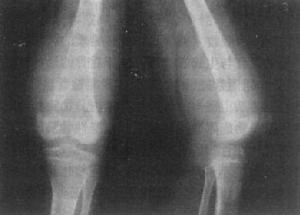

流痰是一种发生于骨与关节间的结核性化脓性疾病。因其脓形成后,可流窜于病变附近或较远的空隙处形成脓肿,破损后脓液稀薄如痰,故名日流痰。又以其后期可出现虚痨症状,又有骨痨之称。好发于儿童和青年,患者常有肺结核病史。可治疗。[1]